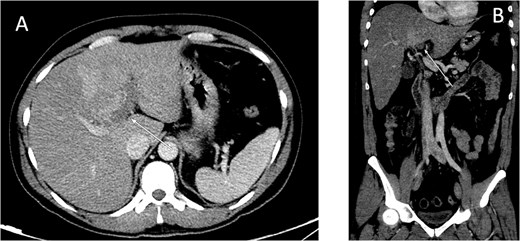

An ultrasound of the abdomen showed an impacted stone at the neck of the gallbladder with acute cholecystitis. The patient was admitted and started on IV antibiotics. He developed tachycardia reaching 110 bpm and had a high white blood cell count; therefore, the decision was made to proceed with a contrast-enhanced computed tomography (CT) scan, which showed evidence of acute cholecystitis and left PVT (Fig. 1). The medical team was consulted, and IV heparin without bolus was started. The gastroenterology team was consulted for his high bilirubin levels and advised for magnetic resonance cholangiopancreatography (MRCP), which was done the next day and confirmed the findings of left PVT (Fig. 2). MRCP also showed a micro perforation of the gallbladder and no biliary obstruction or stones (Fig. 3).

MRCP T1-weighted images: (A) axial cut; (B) coronal cut. Arrow indicates left portal vein thrombosis.